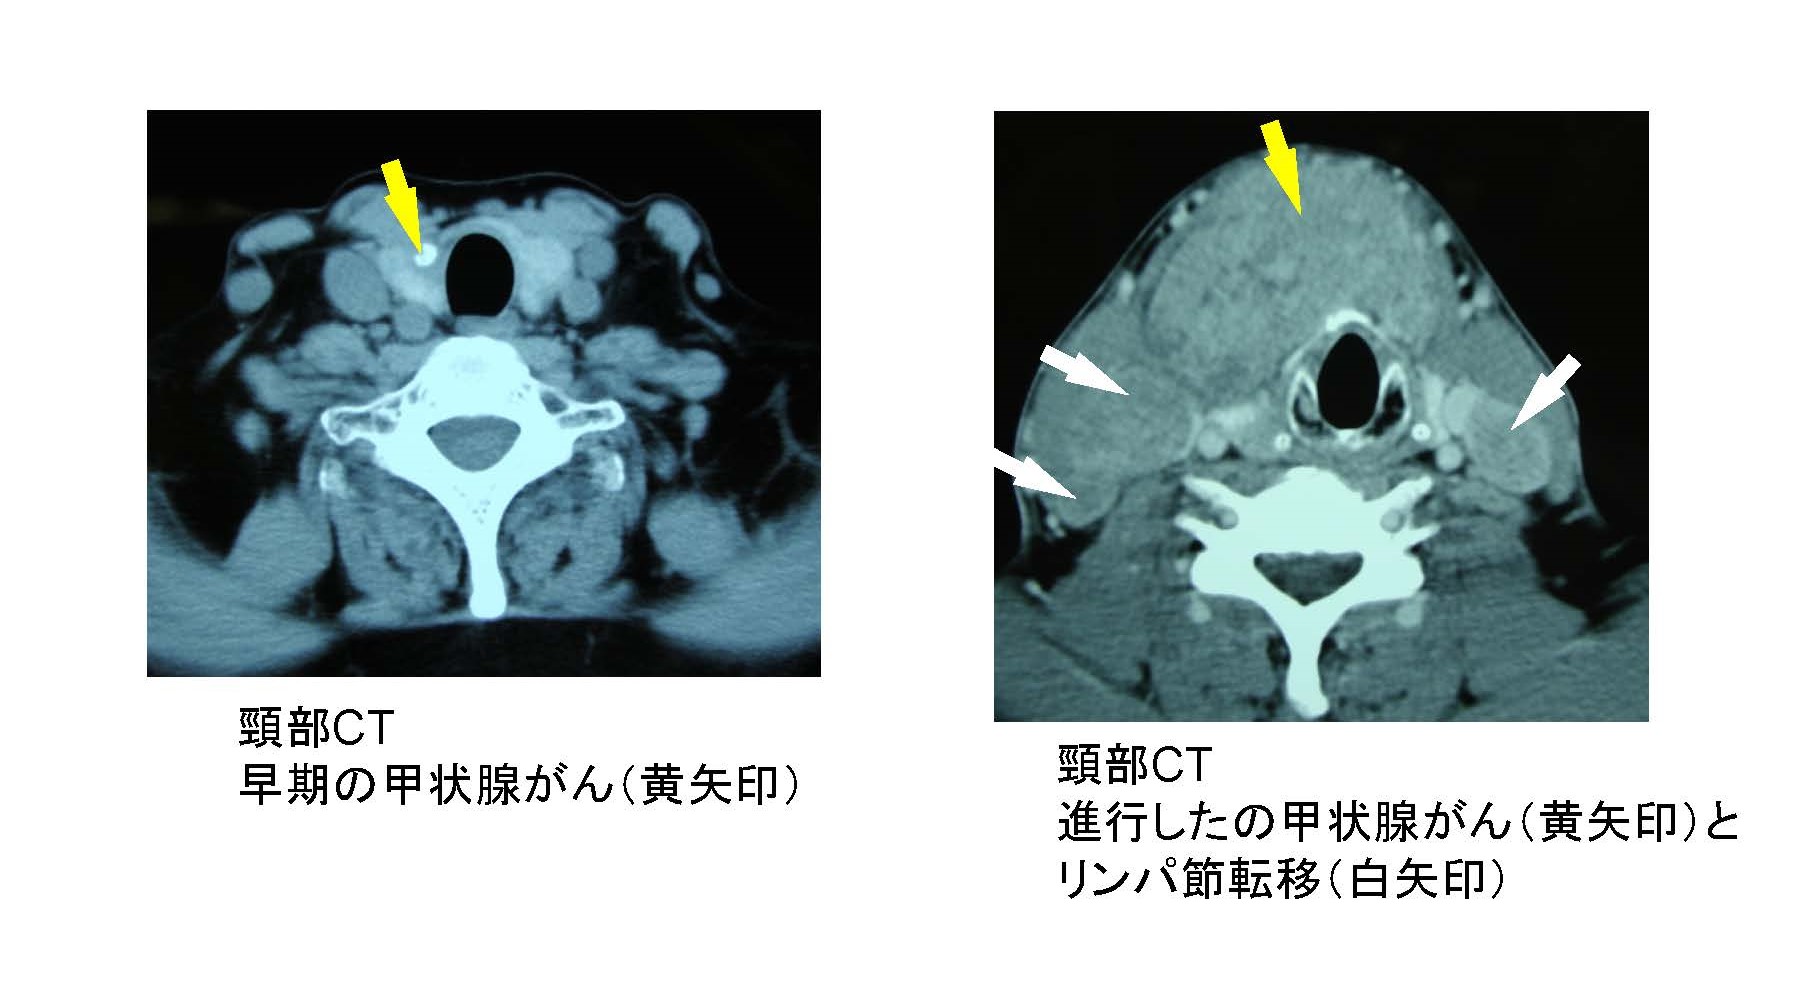

- 甲状腺がん